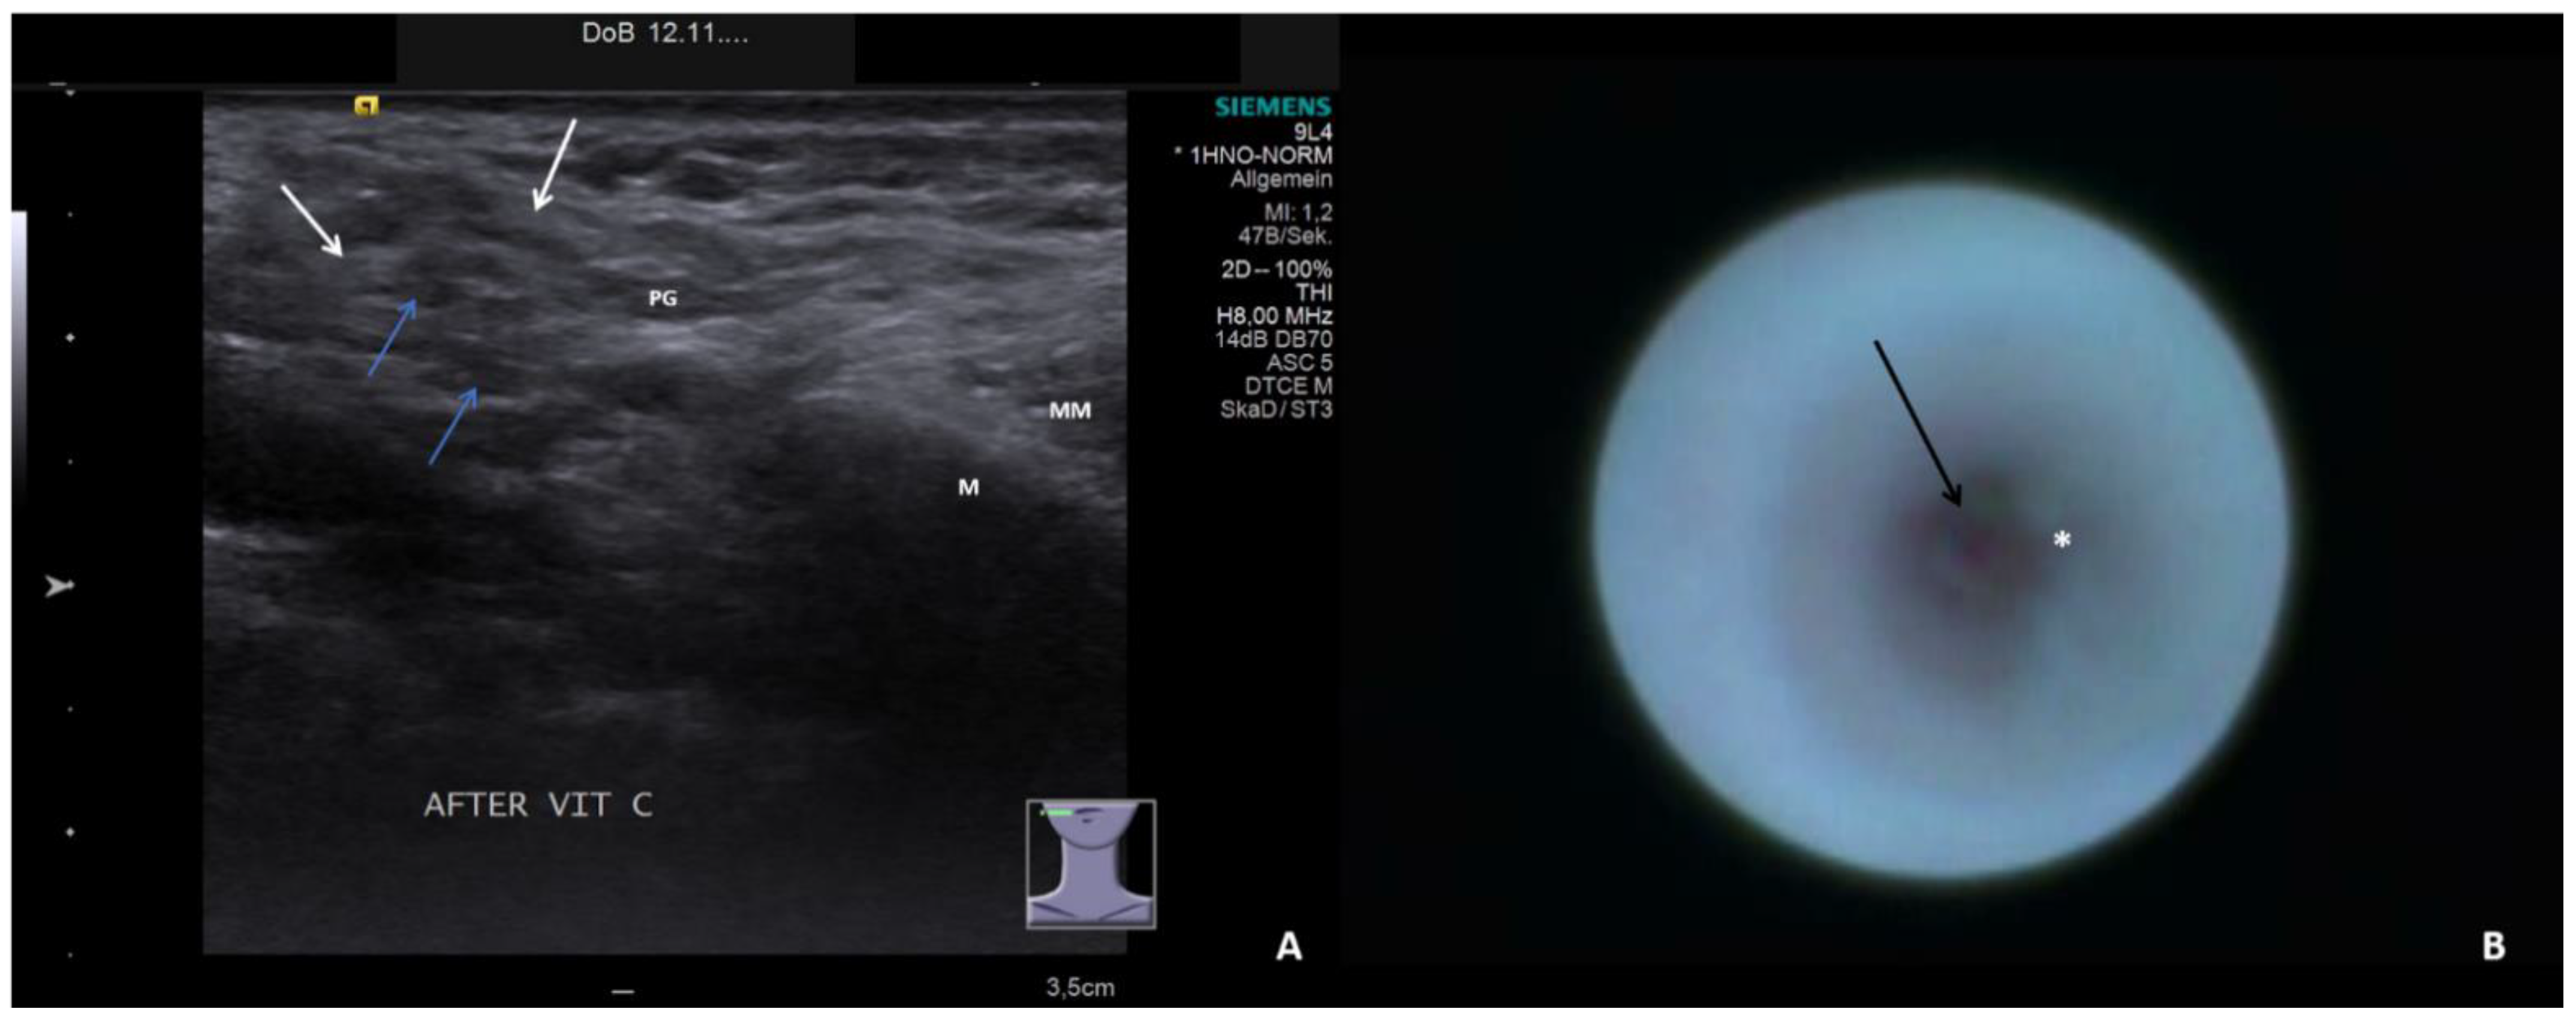

- Sialodochitis with a tendency toward duct narrowing (SD + Sten: SD and thickness of the duct wall with a tendency toward luminal narrowing; Figure 2B; Supplementary Video S2)